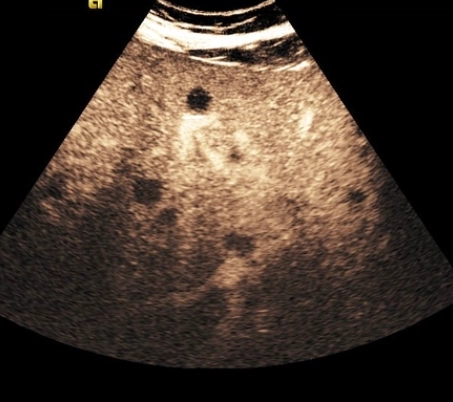

Nang lách (Splenic Cyst)

U máu lách (Splenic hemangioma)

U mạch bạch huyết lách (Splenic lymphangioma)

Lymphoma lách (Splenic lymphoma)

Hamartoma lách (Splenic hamartoma)

U mạch máu ác tính lách (Splenic angiosarcoma)

Di căn lách (Splenic metastases)

Tạo máu ngoài tủy tại lách (Extramedullary hematopoiesis in the spleen)